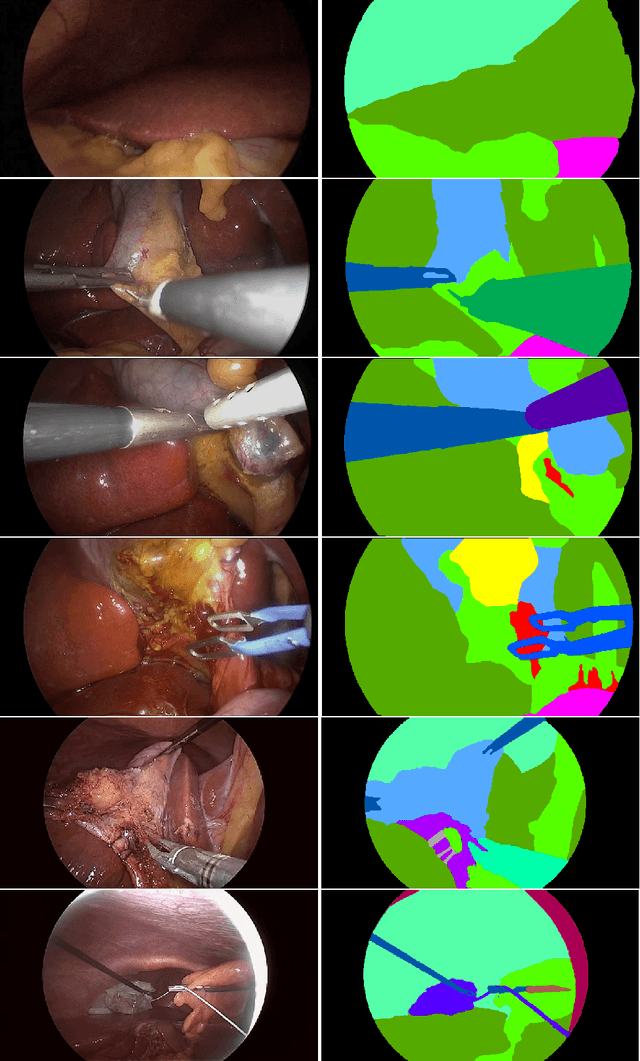

Abstract:Autonomous surgical procedures, in particular minimal invasive surgeries, are the next frontier for Artificial Intelligence research. However, the existing challenges include precise identification of the human anatomy and the surgical settings, and modeling the environment for training of an autonomous agent. To address the identification of human anatomy and the surgical settings, we propose a deep learning based semantic segmentation algorithm to identify and label the tissues and organs in the endoscopic video feed of the human torso region. We present an annotated dataset, m2caiSeg, created from endoscopic video feeds of real-world surgical procedures. Overall, the data consists of 307 images, each of which is annotated for the organs and different surgical instruments present in the scene. We propose and train a deep convolutional neural network for the semantic segmentation task. To cater for the low quantity of annotated data, we use unsupervised pre-training and data augmentation. The trained model is evaluated on an independent test set of the proposed dataset. We obtained a F1 score of 0.33 while using all the labeled categories for the semantic segmentation task. Secondly, we labeled all instruments into an 'Instruments' superclass to evaluate the model's performance on discerning the various organs and obtained a F1 score of 0.57. We propose a new dataset and a deep learning method for pixel level identification of various organs and instruments in a endoscopic surgical scene. Surgical scene understanding is one of the first steps towards automating surgical procedures.